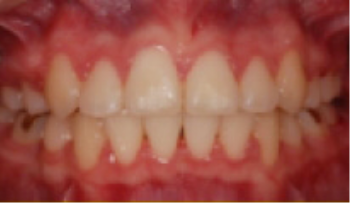

• 총생(Crowding) 치아가 삐뚤게 남.

Before

After